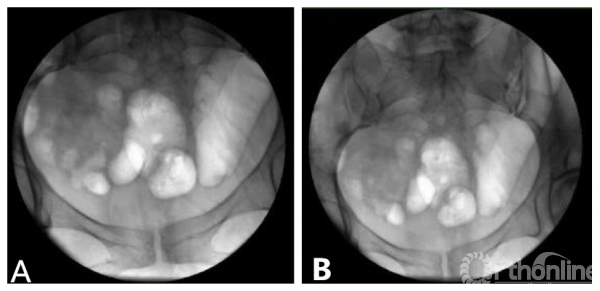

图-1 透视管球正位像显示骨盆视野的区别 A. 9英尺;B. 12英尺

★透视机选择:常用透视影像接收器有9或12英寸两种,两者X线管球照射强度和清晰度接近,但显像的范围有一定的差距,相较12英寸范围更大。因此如想一次照射显示更大范围骨盆结构,建议使用12英寸。12英寸透视的缺点是机身较重,机器移动有一定困难。小机器操作相对简单、便捷,但是影像显示范围较小(图-1)。